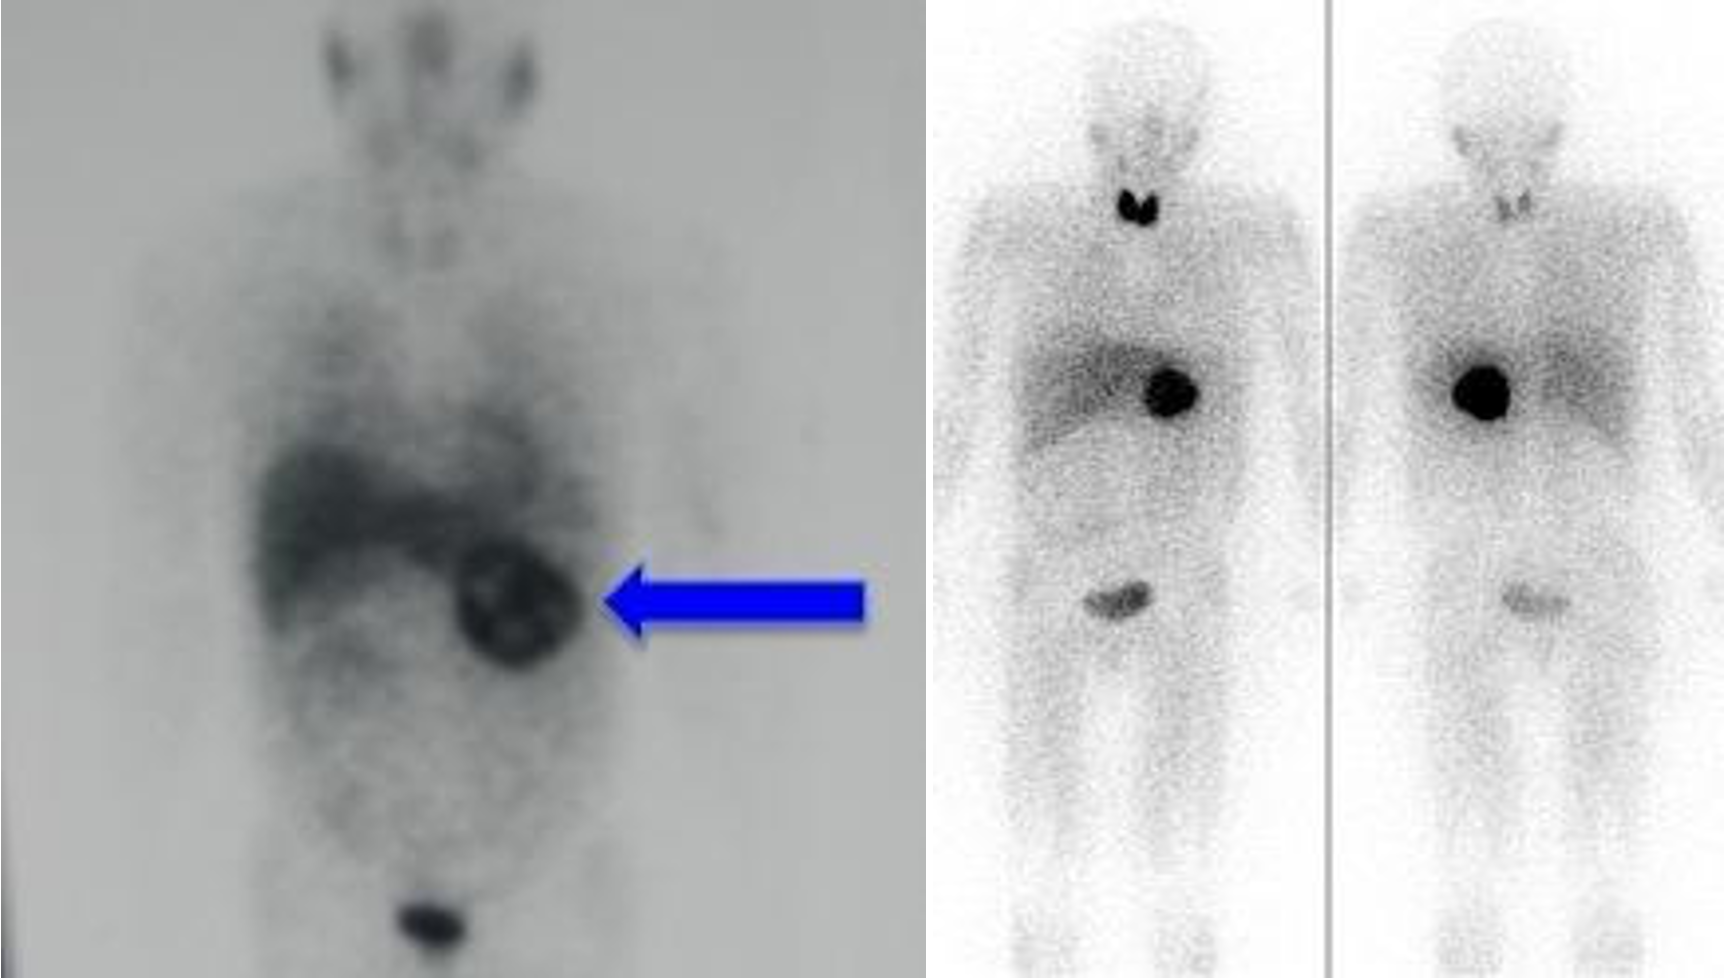

NUCLEAR SCAN

cold nodule = malignancy

PET SCAN

annual follow up

- soft tissue sarcoma -

- lung cancer metasteseses to bone

HIDA SCAN

gall - 100% - diff acute cholecystitis

2) negative

3) positive